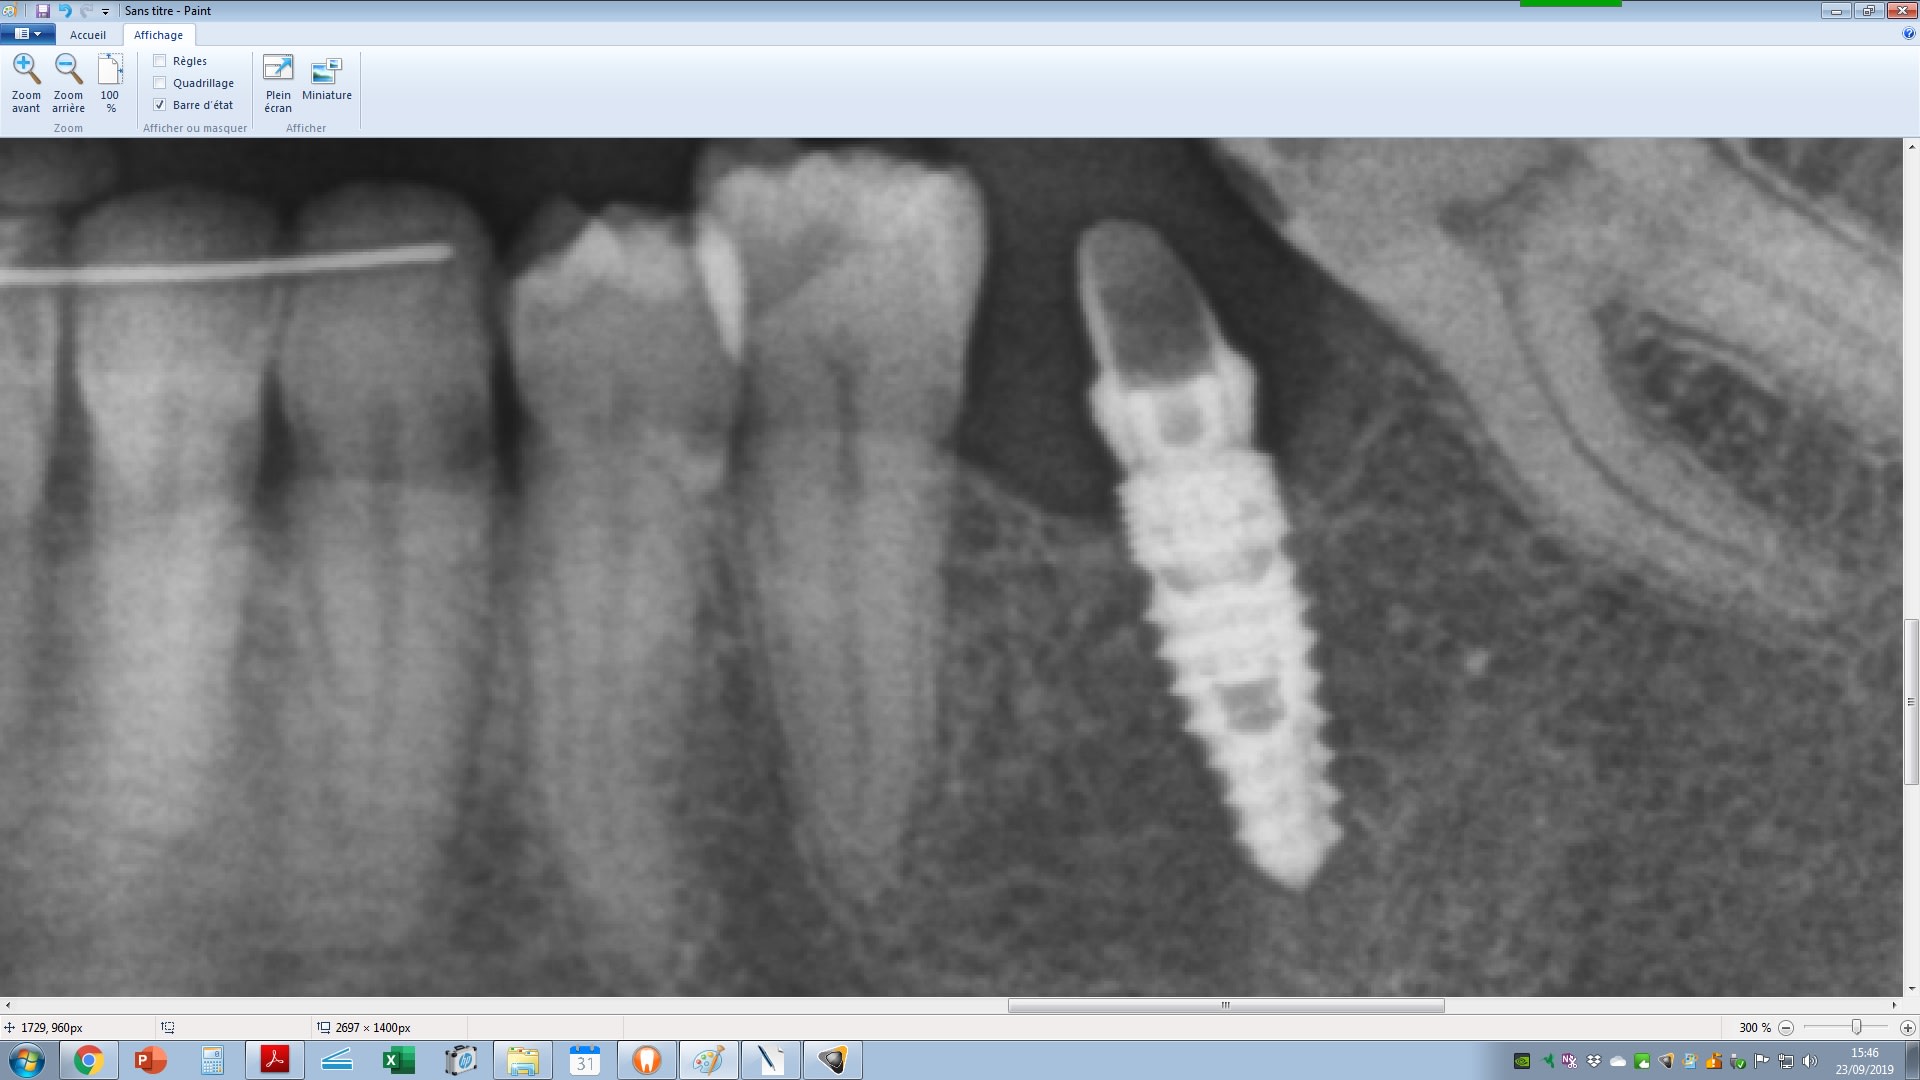

l'implant est conique, le col a des micros filets, l'apex est pointu, et la connexion est interne.

je pense pas que ça soit un dentaurum

le tiologic à une spire dédoublée et le tiolox n'a pas de microspire au col.

sur la radio la spire est simple et le col est microspiré

m'est d'avis que tu aurais une RETRO et non un crop de la pano tu verrais plus de détails....

et donc on aurais une meilleure base de recherche....

je me demande si c'est pas un paltop

son prat m'a envoyé une retro, mais c'est pas mieux que la pano